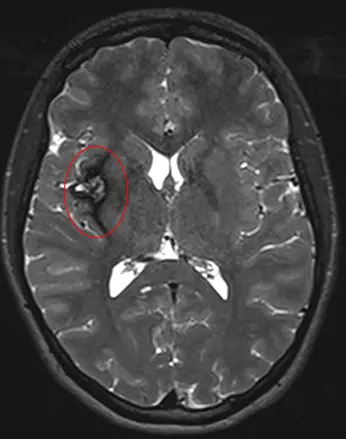

Cavernomas are enlarged and deformed blood vessels gathered into clusters. These clusters, called angiomas, may look bubbly, like raspberries. A cavernoma can appear in the brain, spinal cord or other parts of the nervous system and body, including on the skin and eye.

Cerebral cavernous malformations, or CCMs, are abnormal blood vessels that gather into clusters about the size of a raspberry.

Cavernomas are diagnosed using magnetic resonance imaging (MRI). Treatment for cavernomas includes: